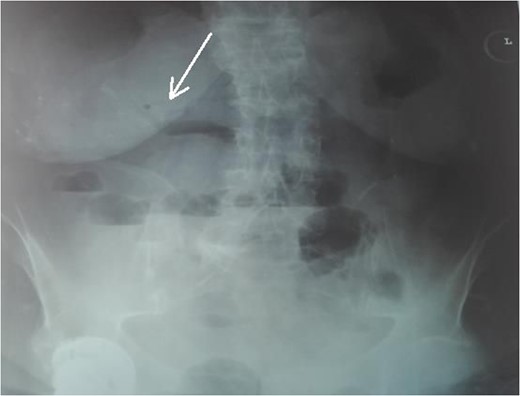

An 87-year-female patient was admitted to emergency department complaining about vomiting for the past 7 days with mild abdominal pain. The patient was hemodynamically stable, had sluggish bowel sounds and soft abdominal wall with mild tenderness. The patient also suffered from atrial fibrillation, heart failure, myelodysplastic syndrome, hiatus hernia and cholelithiasis. The findings of the laboratory tests were unremarkable. Plain chest and abdominal radiograms revealed hiatus hernia with gastric dilation (Fig. 1), a few air-fluid levels and pneumobilia, with delineation of extrahepatic and intrahepatic bile ducts by air (Fig. 2). A nasogastric tube was inserted, which drained biliary content. An abdominal computed tomography (CT) scan revealed the presence of air in the intrahepatic bile ducts, free air and leakage of oral contrast agent in the hepatic hilum and subhepatic space and an impacted gallstone in the third portion of the duodenum (Figs 3 and 4). The diagnosis of cholecystoenteric fistula and proximal gallstone ileus was set.

Abdominal CT scan (coronal plane). The long arrow shows the impacted gallstone and the short arrow shows the free air and the leakage of oral contrast agent.